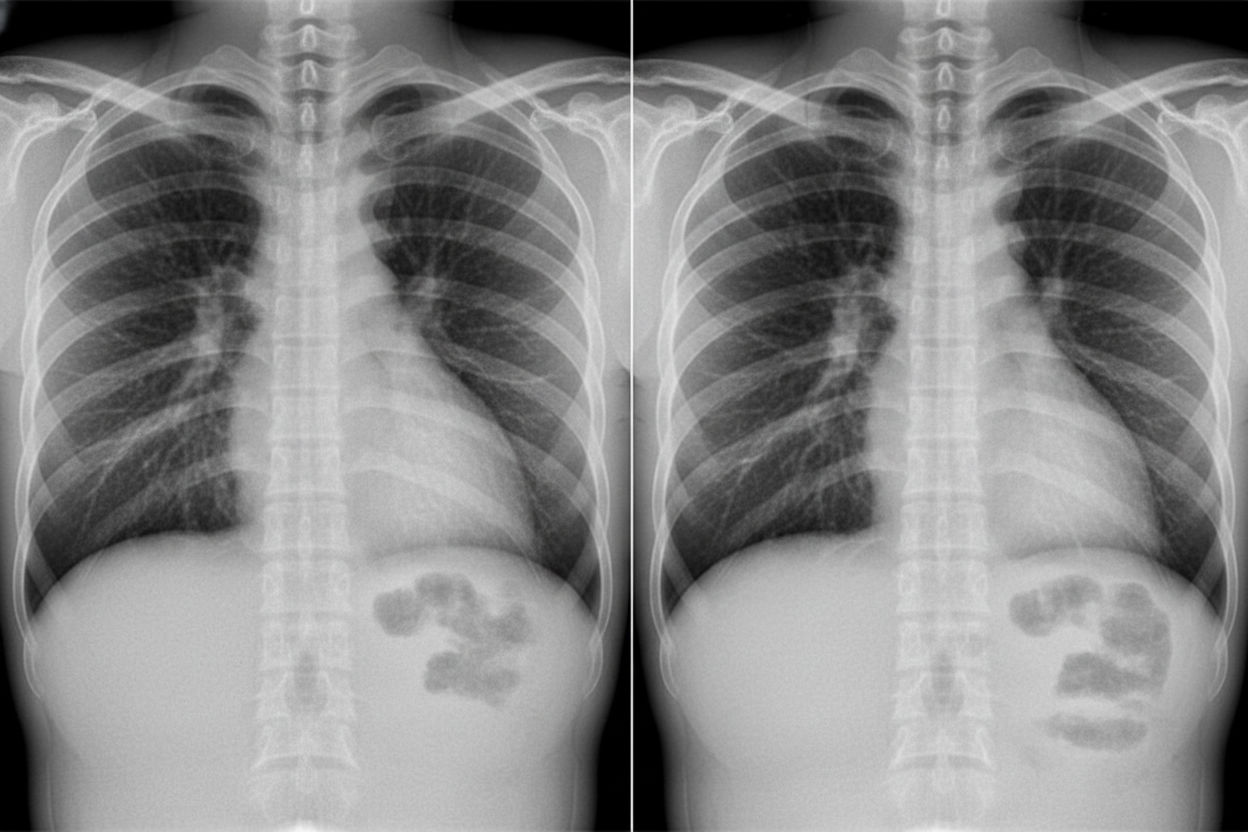

A patient presents with acute onset high-grade fever, chills, productive cough with rusty-colored sputum, and pleuritic chest pain. The chest X-ray is shown below. What is the most likely diagnosis?

Explanation: ***Pneumococcal Pneumonia*** - **Lobar consolidation** on chest X-ray is the classic radiographic pattern for **Streptococcus pneumoniae** pneumonia. - Most common cause of **community-acquired pneumonia** in immunocompetent adults, presenting with homogeneous consolidation affecting an entire lobe. *Tuberculosis* - Typically presents with **upper lobe involvement** and **cavitation** on chest imaging, not lobar consolidation. - Associated with **night sweats**, **weight loss**, and **chronic cough** over weeks to months. *Klebsiella pneumonia* - Usually causes **upper lobe consolidation** with **bulging fissure sign** and potential **cavitation**. - More commonly seen in **alcoholics** and **diabetics**, with thick, bloody sputum production. *Pneumocystis pneumonia* - Characterized by **bilateral interstitial infiltrates** or **ground-glass opacities**, not lobar consolidation. - Occurs almost exclusively in **immunocompromised patients** (HIV, organ transplant recipients).